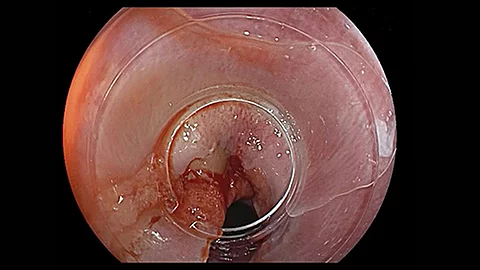

PEG-KomplikationVerschluss des Ostiums durch Clip-System

Im neuen Video präsentiert PD Dr. Jochen Weigt den seltenen Fall einer schweren lokalen Komplikation nach PEG-Anlage. Bei einer 61-jährigen Patientin wurde eine PEG gelegt. Sechs Tage später stellte sie sich mit Wundproblemen und Schmerzen vor.